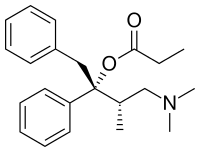

- Dextropropoxyphene (propoxyphene)

Structures

| Phenalkoxams | ||||

Dextropropoxyphene |